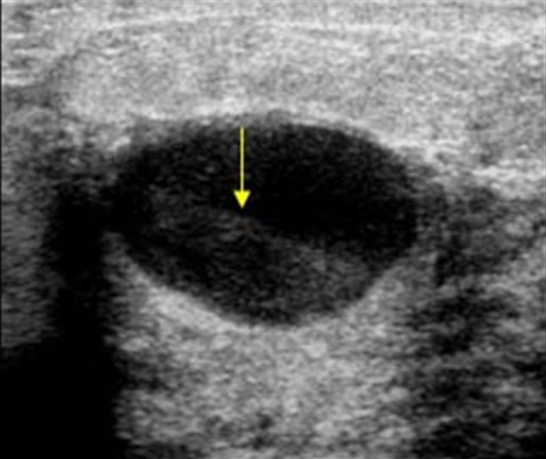

Que tipo de tumor este nódulo sugere?

A

MALIGNO

Características que sugerem malignidade ao USG?

• Misto

• Heterogêneo

• Mal delimitado

• Diâmetro AP > latero-lateral

• Sombra acústica posterior

How well did you know this?